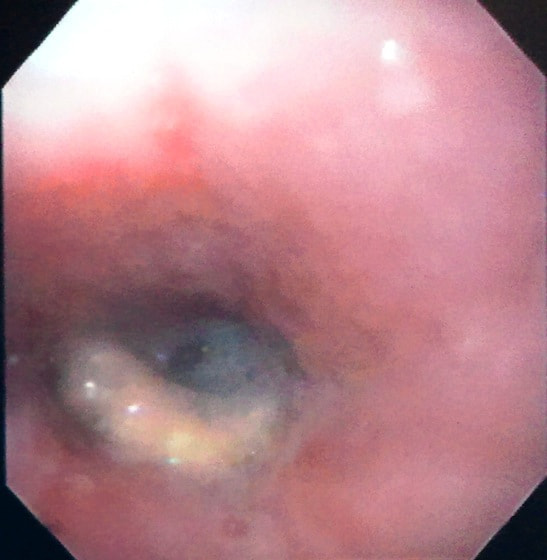

経過:超音波検査にて直腸壁の肥厚(5㎜)が認められた。また、直腸検査で直腸全周に結節状病変を触知し、出血も確認された。消炎剤、抗生剤、整腸剤による治療への反応が長期的に悪いため、生検も含めた内視鏡検査を実施した。

内視鏡検査:肛門付近の直腸全周に、炎症および出血を伴う結節状病変を多数認めた。

病理検査:直腸の病変は、良性の非腫瘍性病変の一つである“炎症性ポリープ”と診断された。

診断後経過:炎症性ポリープは多発する傾向や腫瘍に転化する可能性があるため、消炎剤、抗生剤、整腸剤による内科療法を継続しながら、現在プルスルー法による外科的摘出術を検討中。